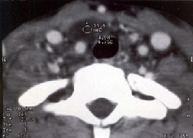

Imagen TAC, caso inusual, quiste paratiroideo, se trataba de una paciente adolescente con una lesión quística supraesternal inferior con relación al lóbulo tiroideo, sobre la carótida primitiva y que se continuaba hacia el mediastino superior